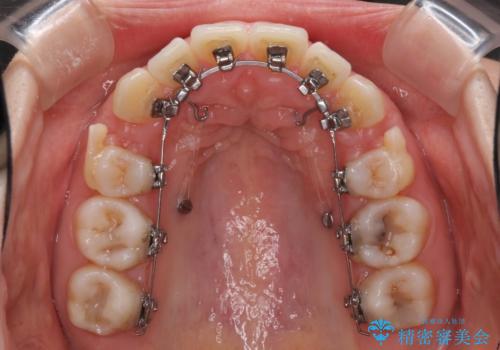

- ハーフリンガル

目立たない装置を希望されたので、上顎が裏側装置のハーフリンガルを選択し、上下左右の小臼歯(計4歯)を抜歯して矯正治療を行うこととしました。

治療期間の目安は2年半~3年間でしたが、咬み合わせにより上顎装置が頻繁に脱落してしまい、治療期間が長期化してしまいました。